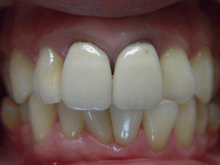

オールセラミックス

金属を使わずに全てセラミックを使用し、光の透過性を上げる事により自然な白い歯に回復させる方法です。

現在では土台から白い材質(ファイバーポストなど)の物を使用することにより、さらに透明感が増し天然歯に近似しています。

オールセラミックは近年進化を遂げており、強度や接着性がかなり改善され、審美的にとても優れたものと成って来ております。

オールセラミックにも色んな種類がありますが、当院ではe-max(二ケイ酸リチウムガラスセラミック、)ジルコニアセラミックスを採用しています。

症 例